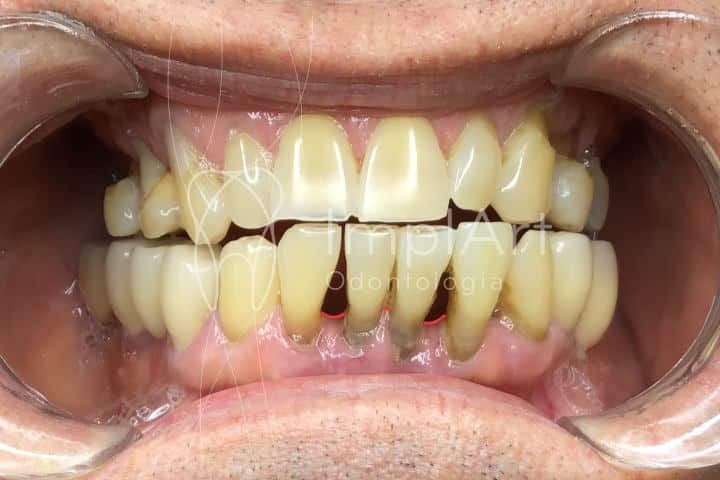

Blackspace ou buraco negro dental é um espaço escuro entre os dentes com formato triangular invertido que surge especialmente na linha da gengiva. Alguns pacientes podem se sentir incomodados pela estética dental. Em casos moderados, temos o tratamento de preenchimento com ácido hialurônico. Pouco tem se falado sobre esta característica, e vamos contar para você um pouco o que é o blackspace e quais o tratamentos indicados. Veja a seguir:

Entre as principais causa para o surgimento de um blackspace dental estão: aumento gengival, pouca espessura de rebordo ósseo, retração gengival, perda óssea e/ou gengival e ausência de papila interdental.

O blackspace dental não é um problema grave, mas é capaz de gerar um prejuízo estético para o sorriso e eventualmente causar problemas fonéticos e retenção de alimentos.

O blackspace dental não é a mesma coisa que o diastema. O blackspace é um espaço negro de forma triangular invertida. O diastema é um espaço retangular entre os dentes com praticamente a mesma largura tanto em toda extensão vertical.